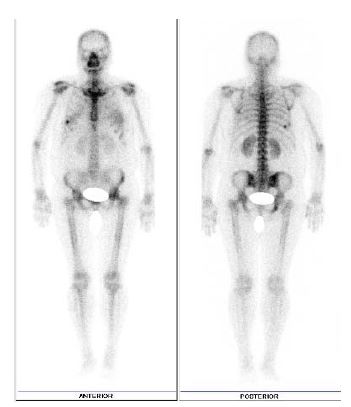

En las Figuras 2 y se aprecia la diferencia entre incluir la medida del pie y omitirlo, observándose que la primera tiene una mejor resolución y visualización de todas las estructuras óseas, facilitando una evaluación correcta para un diagnóstico gammagráfico más preciso.

Figura 3. Gammagrafía ósea en la que no se incluyó la medida del pie, hay falta de visualización adecuada de los pies.